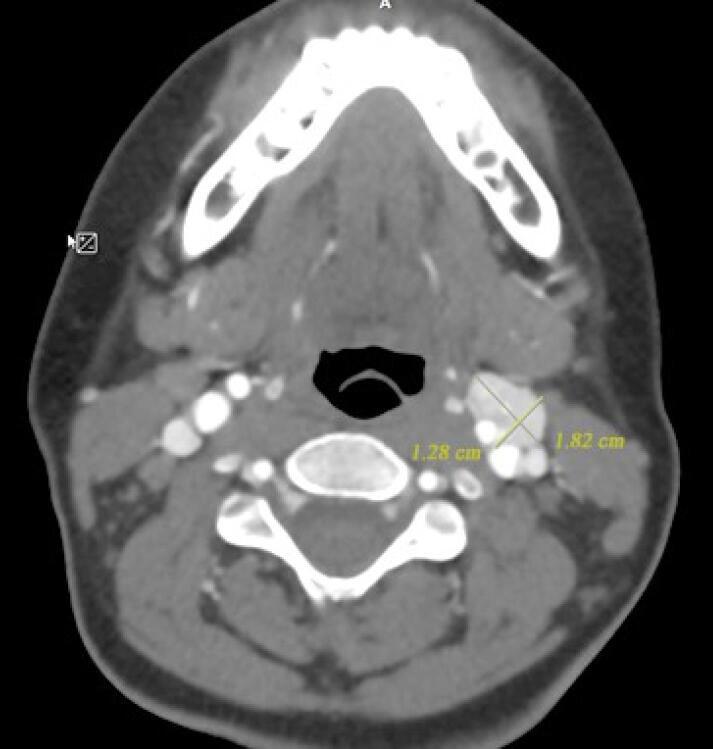

This case report presents a 10-year-old patient diagnosed with pheochromocytoma/paraganglioma syndrome type 1 (PPGL1), underlined by a novel heterozygous pathogenic variant (c.154_161del, p.ser52Profster14) in the gene. Initially, the patient manifested symptoms unusual for pheochromocytoma, including polyuria and polydipsia; however, further diagnostic investigations revealed a pheochromocytoma (PCC) tumor in the adrenal gland. Subsequently, whole exome sequencing (WES) test identified a pathogenic frameshift variant in the gene, strongly suggestive of PPGL1. This study highlights the importance of considering atypical symptoms in diagnosing rare pediatric pheochromocytoma/paraganglioma tumors and underscores the value of genetic testing in identifying underlying genetic causes, thereby facilitating personalized management of the condition.

本病例报告介绍了一位 10 岁患者,被诊断为 1 型嗜铬细胞瘤/副神经节瘤综合征(PPGL1),其 基因中存在一个新的杂合致病性变异(c.154_161del,p.ser52Profster14)。最初,该患者表现出不同于嗜铬细胞瘤的症状,包括多尿和多饮;然而,进一步的诊断研究发现肾上腺有嗜铬细胞瘤(PCC)肿瘤。随后,外显子组测序(WES)检测发现 基因中的一个致病性移码变异,强烈提示为 PPGL1。本研究强调了在诊断罕见儿科嗜铬细胞瘤/副神经节瘤肿瘤时考虑不典型症状的重要性,并强调了基因检测在确定潜在遗传病因中的价值,从而有助于对该疾病进行个性化管理。